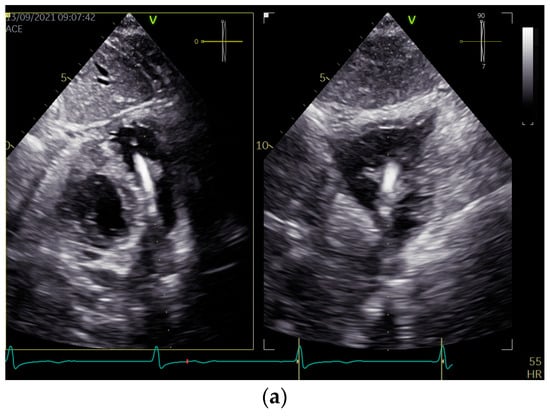

As the blood cultures (aerobic and anaerobic) were repeatedly negative, the empirical treatment of suspected infective endocarditis was not implemented. In TTE, in addition to a thickened RV lead with attached mobile structures, the features of the lead dislocation into the PA were revealed via an echo of the lead’s presence with intensive doppler color of pulmonary regurgitation, visualized in PA (Figure 1, Supplementary Videos S1 and S2).

Figure 1.

Two-dimensional transthoracic echocardiographic views show the implantable cardioverter-defibrillator (ICD) lead located in the pulmonary outflow tract (a), causing pulmonary insufficiency (b). The examination was performed using a GE VIVID E95 machine (GE ultrasound System, Horten, Norway) equipped with an active-matrix 4D volume phased array transducer (4Vc-D). Echo sets were obtained using subcostal bi-plane (a) and parasternal short-axis (b) views.